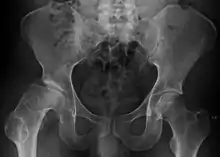

X ray of deformity by Legg–Calvé–Perthes disease of the right hip (left side of X-ray)

Children younger than six have the best prognosis, since they have time for the dead bone to revascularize and remodel, with a good chance that the femoral head will recover and remain spherical after resolution of the disease.[19] Children who have been diagnosed with Perthes' disease after the age of ten are at a very high risk of developing osteoarthritis and coxa magna. When an LCP disease diagnosis occurs after age eight, a better outcome results with surgery rather than nonoperative treatments.[20] Shape of femoral head at the time when Legg-Calvé Perthes disease heals is the most important determinant of risk for degenerative arthritis; hence, the shape of femoral head and congruence of hip are most useful outcome measures.[7]